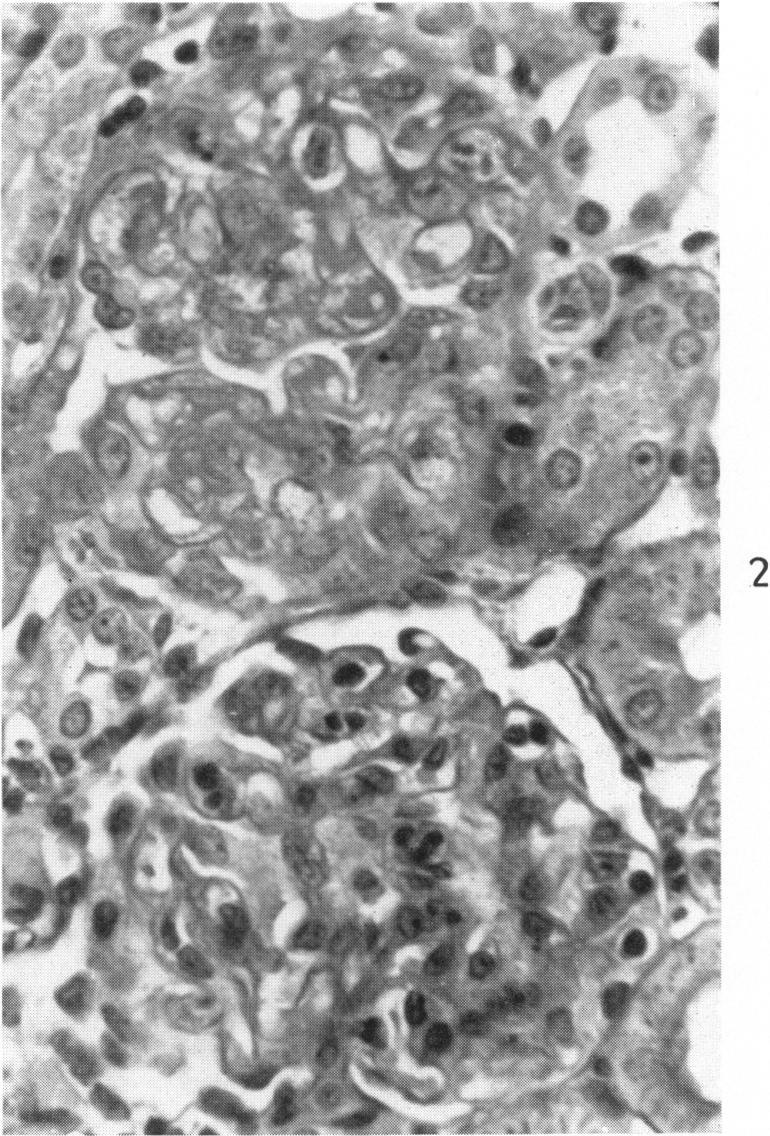

Nephrotoxic serum nephritis in the rat. Electron and light microscopic studies.

Am J Pathol. 1960 Dec;37(6):729-49.

PMID:13693531